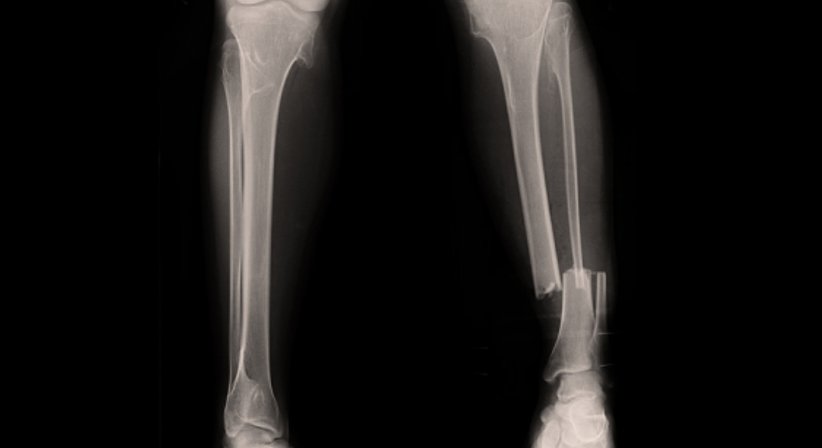

In der Regel wird zwischen verschiedenen Bruchformen unterschieden. Sogenannte glatte Quer- oder Schrägbrüche zählen dabei zu den unkompliziertesten Brüchen.

Zudem gibt es Mehretagenbrüche, Längsbrüche, Trümmerbrüche und offene Brüche.

Als Facharzt für Unfallchirurgie bin ich auf die konservative und operative Behandlung von knienahen Knochenbrüchen (z.B. Schien- und Wadenbeinbruch, Unterschenkelfraktur, etc.) spezialisiert.